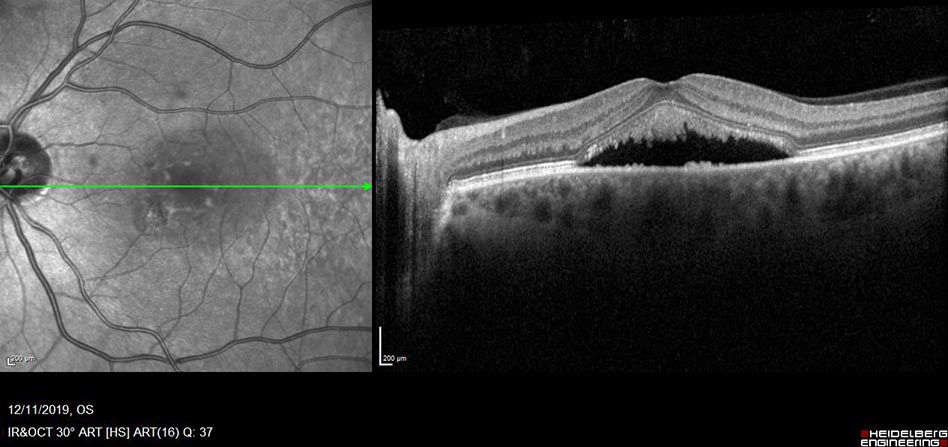

There are two types of AMD, a ‘wet’ or neovascular form identified by the presence of fluid in the retina and a ‘dry’ form which presents no fluid. Treatments vary for each specific retinal condition, these could include intravitreal into the eye, drops administered topically, IV infusions of laser to the retina. All of these treatments can be monitored with the use of OCT scanning.

WET OCT

OCT scan pre treatment